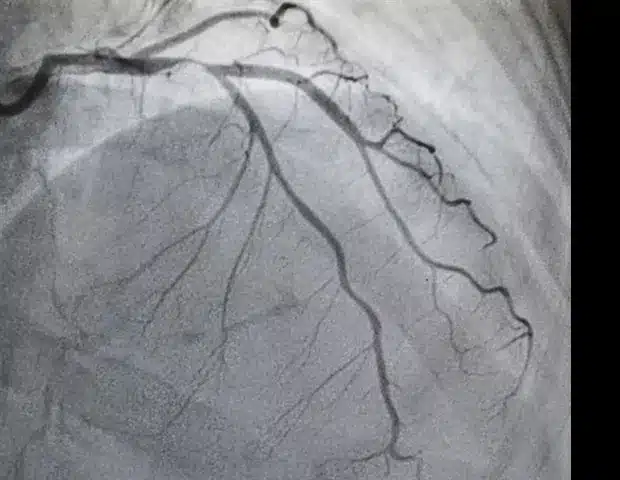

Aortic stenosis is a prevalent heart valve condition that progresses over time. Untreated severe cases lead to death in half of symptomatic patients within two years. Symptoms such as fatigue, shortness of breath, and dizziness often mimic normal aging, delaying diagnosis. Older Black Americans experience lower diagnosis rates despite elevated mortality, highlighting the urgency for equitable screening.